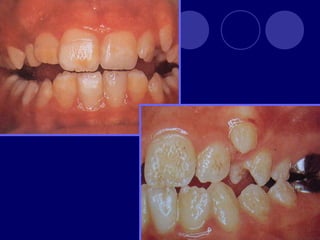

ANOMALÍAS DE ESTRUCTURA AMELOGENESIS IMPERFECTA: (Hipoplásico, hipocalcificado Hipomaduro)  DISPLASIA AMBIENTAL DEL ESMALTE

Diagnóstico:  Historia familiar Distribución de la alteración (no. De dientes, disposición V= genética y H= ambiental)  Identidad del agente causal

AMELOGENESIS IMPERFECTA  Hipoplásico: Zonas ausentes de esmalte  Afecta más a caras vestibulares  Esmalte: blanco amarillento y marrón claro, consistencia dura, fosas y surcos oscuras, delgado  Hipocalcificado:  Cualitativo  Esmalte frágil, fácil de desprender  Rx: falta de contacto entre dentina, esmalte  Hipomaduro:  Disminución en el contenido mineral  Esmalte blando y rugoso, veteado de blanco a marrón (esmalte en copos de nieve)  Más frecuente en caras vestibulares y dientes superiores

DISPLASIA AMBIENTAL DEL ESMALTE HIPOPLASIA POR INGESTA DE FLÚOR: fluorosis, manchas opacas, esmalte sin brillo(leve=lechoso, graves=amarillo/café) .

 DÉFICIT NUTRICIONAL  ENFERMEDADES EXANTEMÁTICAS INFECCIONES PRENATALES:  Sífilis congénita  Rubéola  NEFROPATÍAS  ENDOCRINOPATÍAS